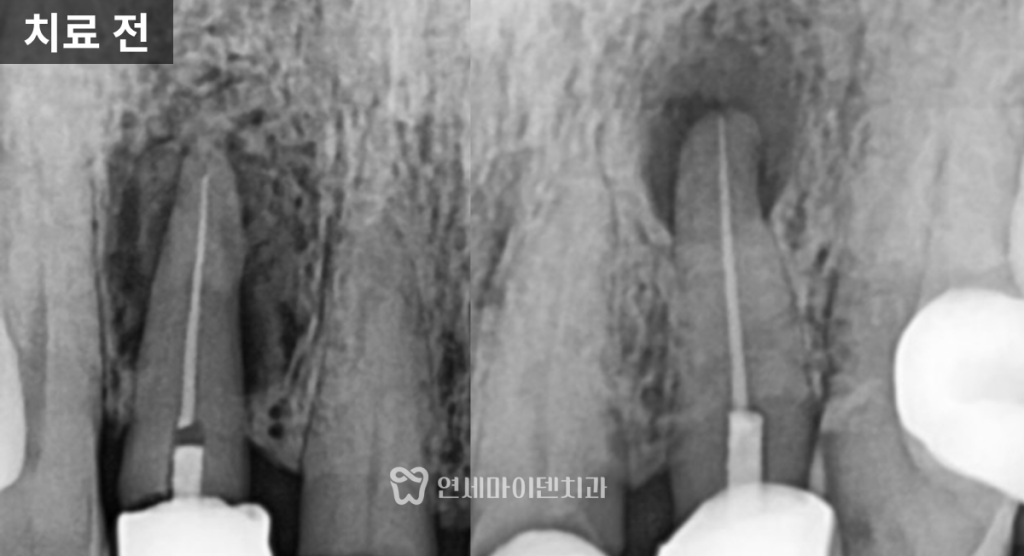

정밀 촬영 결과

두 개의 앞니 뿌리 끝, 즉 치근단 부위에서

뚜렷한 염증 소견이 확인되었습니다.한쪽 치아는

뼈 손상이 심해 예후가 불량한 상태였고,

다른 한쪽은

염증이 국소적으로 제한되어 있어

반면, 보존이 가능하다고 판단된 앞니는

신경치료를 진행했고

내부를 철저히 소독한 뒤

경과를 관찰했습니다.치료 결과

임플란트로 치료한 앞니는

안정적으로 자리 잡았고,신경치료를 시행한 치아는

치근단 낭성 병변이

자연스럽게 치유되면서

추가적인 치근단 수술 없이

회복을 확인할 수 있었습니다.